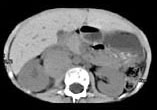

- 多项选择题男,5 岁, 消瘦、贫血、纳差和腹部包块3个月,CT检查如图, 下列说法正确的是  (    )

- A、右侧腹腔内可见一巨大软组织肿块影,其边界欠清楚

- B、肿块密度不均匀,可见片状的较高密度,考虑为出血,也可见点状的钙化影

- C、该病灶来源于肝脏,考虑为肝母细胞瘤

- D、该病灶来源于右肾上腺,考虑为神经母细胞瘤

- E、该病灶来源于右肾,考虑为肾胚胎瘤